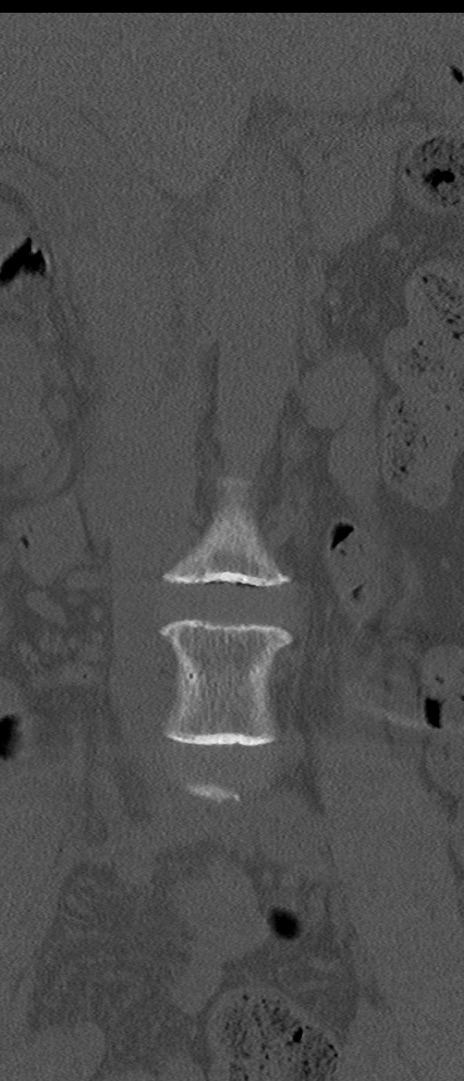

【整形】TIPS症例4 腰椎CT(冠状断像)

腰椎CT